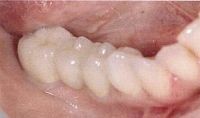

当院のインプラント症例(1本失った場合)

インプラント症例(1本失った場合)②術前

インプラント症例(1本失った場合)②術後